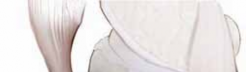

B. The osteotomy plate is trialed. In this case, the posterior tine is in place and the anterior tine has been removed. C. Second-gener-ation locking plate in place. The white arrow points to the mark on the plate verifying the slope from anterior to posterior (ie, the trapezoid is larger posterior B C than anterior). BONE GRAFTING 1. Depending on the preference of the surgeon and patient, the osteotomy must be packed with bone graft and the medial cortical margins reinforced with tricortical iliac crest graft.

Autograft Iliac Crest and Bone Grafting

2. The benefit of autograft iliac crest and bone grafting is that not only are the medial cortical margins of the osteotomy reinforced, but all of the bone graft contains hematopoietic elements and the entire bone formation cascade (

TECH FIG 6A

).

3. The difficulty with this technique is that it is necessary to prep out the iliac crest, and some morbidity results from taking the iliac crest. Although the morbidity is minimal, there is the possibility of postoperative infection, seroma, and pain.

Allograft Iliac Crest and Autograft Cancellous Bone Graft

4. The allograft iliac crest is fashioned into wedges that sit anterior and posterior to the plate.

5. The tricortical iliac crest helps to restore the medial cortical margins (

TECH FIG 6B

6. The autologous cancellous bone graft can either be obtained from the iliac crest in the standard fashion, or a harvester from the osteochondral autograft transplantation system (OATS; Arthrex, Inc., Naples, FL) can be used to take two plugs of bone from the distal medial femur to pack into the osteotomy site.

A B

TECH FIG 6 • A. Iliac crest autograft shaped into wedges to fit into the osteotomy site. B. Final view of the osteotomy with the iliac crest allograft anterior and posterior to the osteotomy plate, helping to restore the medial cortical margins of the osteotomy.